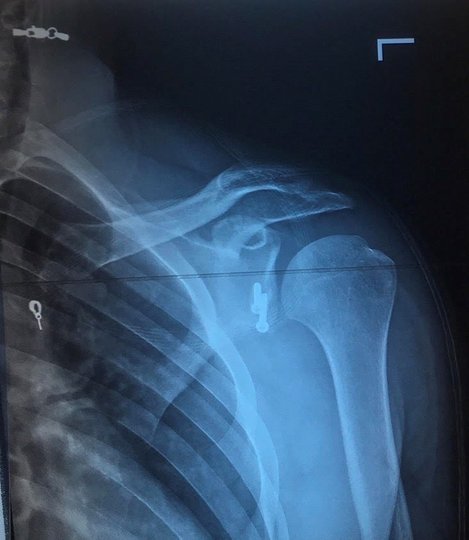

Якщо хочете читати головні новини дня оперативно Додайте ZAXID.NET у вибрані в GoogleХірурги вирішили провести йому операцію по стабілізації плечового суглоба за методом Латерже. «Хірурги відділення артроскопії та малоінвазивних отропедичних втручань Волинської обласної клінічної лікарні вперше провели операцію по стабілізації плечового суглоба з приводу звичного вивиху плеча (операцію Латерже). Таке оперативне втручання має свої труднощі, оскільки є високий ризик пошкодити нервові та судинні структури кінцівки. Саме тому за такі втручання беруться не всі та й не скрізь», – йдеться у повідомленні прес-служби медзакладу.

Відомо, що операція минула успішно, травмований вже може рухати рукою. Наразі пацієнт проходить реабілітацію.